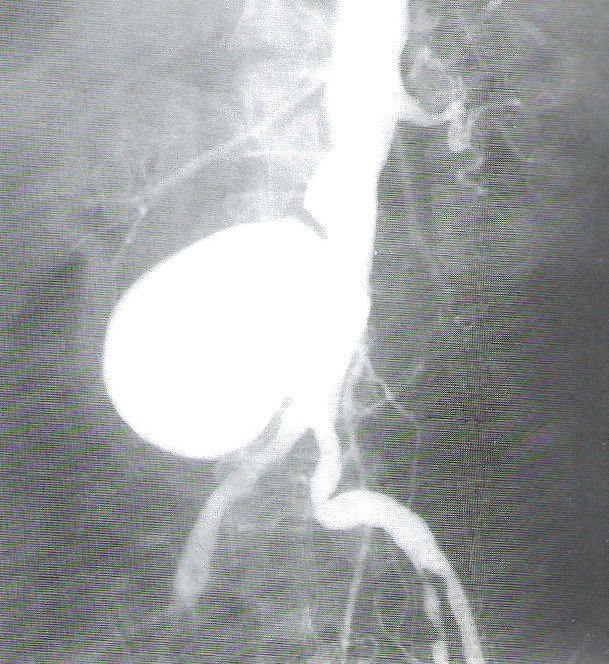

Przedstawiony obraz radiologiczny został zarejestrowany podczas badania jelita

Ilustracja do pytania 23

A. cienkiego po doustnym podaniu środka kontrastującego.

B. cienkiego po doodbytniczym podaniu środka kontrastującego.

C. grubego po doustnym podaniu środka kontrastującego.

D. grubego po doodbytniczym podaniu środka kontrastującego.